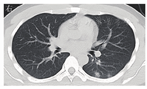

病变发生于两肺各部位,28例患者胸部CT检查主要表现为磨玻璃影21例(75.0%),边缘模糊18例(64.3%),斑点、斑片影17例(60.7%),部分肺纹理增粗、紊乱7例(25.0%),可见条索影7例(25.0%),局部支气管扩张2例(7.1%),淋巴结增多、增粗、血管影、结节影与无壁透亮区各1例(3.6%)。见图1。1例重型肺炎患者入院时两肺纹理增多,两肺内见多发斑片状磨玻璃影,边缘模糊,6 d后肺部病变短期内进展迅速,表现为两肺弥散病灶,磨玻璃影范围增大,双侧胸膜增厚,见图2。